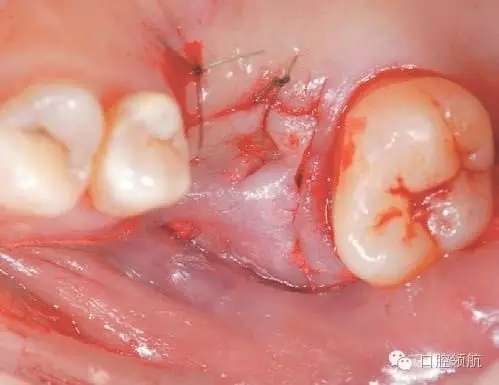

圖2 拔牙后4周,牙齦上皮完全覆蓋拔牙窩。

完全去除拔牙窩內(nèi)的肉芽組織,造成上頜竇底的青枝骨折(圖4),植入骨替代材料行上頜竇底提升術(shù)。

圖4 確認(rèn)上頜竇黏膜增厚消失,而且OMC的換氣和排泄功能已改善后,實施經(jīng)牙槽嵴頂入路的上頜竇底提升術(shù)。按照常規(guī),造成上頜竇底的青枝骨折,提升上頜竇底。